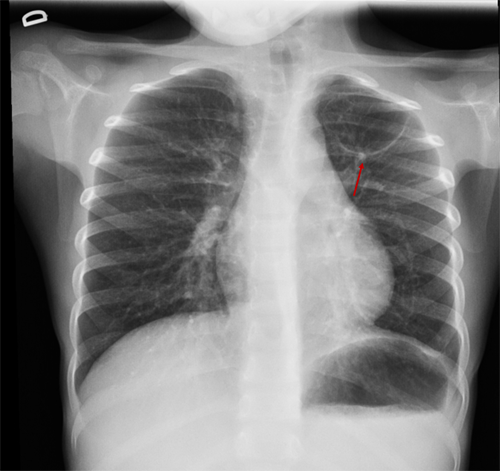

En la revisión 50 días más tarde se aprecia la resolución completa de la consolidación neumónica y una imagen elíptica de 4,3 × 3 cm en el vértice superior izquierdo compatible con neumatocele (Fig. 2). Se opta por tratamiento conservador. En una nueva placa realizada tres meses después se observa una imagen similar, y cuatro meses más tarde (nueve tras diagnóstico inicial) se aprecia, en la radiología torácica convencional, la desaparición de la imagen previa, lo que demuestra resolución espontánea y confirma la sospecha inicial de neumatocele.

| Figura 2. Imagen redondeada en el vértice pulmonar izquierdo, de bordes finos y bien delimitados, de 43 × 31 mm; compatible con neumatocele |